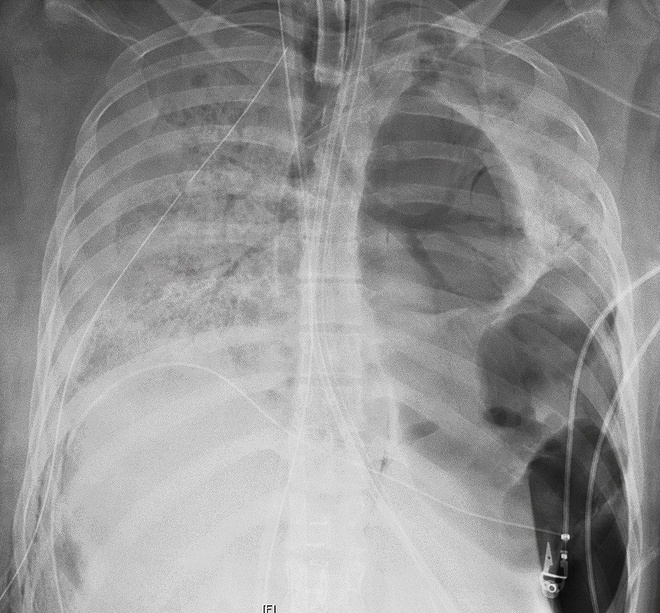

Ca phẫu thuật kéo dài trong 10 tiếng với đầy thách thức, vì virus corona đã khiến phổi của bệnh nhân thủng nhiều lỗ, tới mức phổi gần như dính vào thành ngực, theo bác sĩ Ankit Bharat, người thực hiện ca phẫu thuật.

Hình ảnh chụp X-quang cho thấy phổi bệnh nhân bị thủng nhiều lỗ nhỏ. Ảnh: AP.